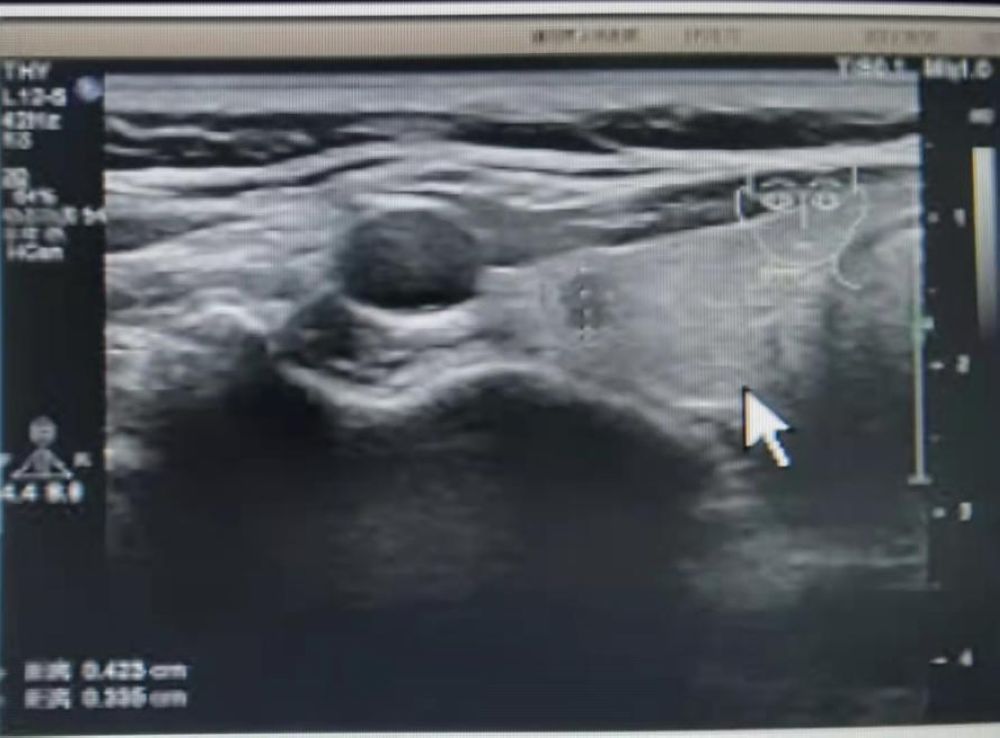

圖1

患者馮某某,女,21歲,大三在讀,在濮陽(yáng)市人民醫(yī)院超聲科進(jìn)行頸部超聲檢查后,發(fā)現(xiàn)右側(cè)葉甲狀腺類結(jié)節(jié)(圖1),并且經(jīng)過活檢穿刺病理為不能除外甲狀腺乳頭狀癌(圖2),這如同一個(gè)晴天霹靂般的壞消息,讓患者難以接受,如花綻放般的年齡,卻要面對(duì)如此殘酷的抉擇。如果選擇手術(shù)切除,術(shù)后頸部的瘢痕、終身服藥的不便成為了現(xiàn)實(shí)難題,讓馮某某難以接受傳統(tǒng)手術(shù)療法。在了解到她的困擾后,濮陽(yáng)市人民醫(yī)院甲狀腺乳腺外科迅速啟動(dòng)科內(nèi)會(huì)診及病例討論機(jī)制,在學(xué)科主任王仁啟主任的提議下,決定采用超聲引導(dǎo)下的射頻消融治療,對(duì)馮某某的惡性結(jié)節(jié)進(jìn)行局部滅活,并且盡可能保留正常腺體。通過術(shù)前評(píng)估,細(xì)致準(zhǔn)備,消融手術(shù)由超聲科主任李亞敏副主任親自主刀。在實(shí)時(shí)超聲的引導(dǎo)下,射頻消融針精準(zhǔn)的進(jìn)入惡性病灶內(nèi),僅用時(shí)3分鐘左右,消融范圍就完全覆蓋病灶并局部擴(kuò)大消融范圍(圖3)。